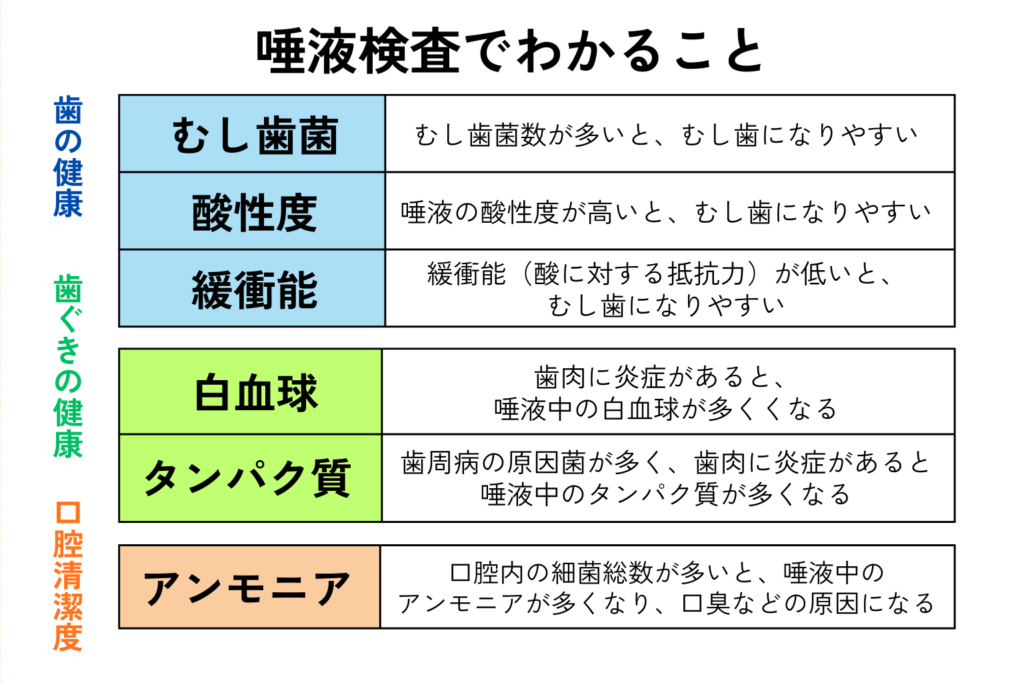

ごとう歯科・矯正歯科クリニックでは、お一人おひとりのお口の状態をより詳しく把握するために、唾液検査を取り入れています。

唾液検査では、

・むし歯菌の量

・唾液の分泌量

・唾液の質(酸を中和する力)

などを調べることができ、見た目だけでは分からない「むし歯リスク」を数値として確認できます。

検査の結果、

「歯磨きをしっかりしているのにむし歯になりやすい」

「甘いものを控えているのに新しいむし歯ができやすい」

といった傾向が分かることも少なくありません。

このように、唾液の量が少ない方、むし歯菌が多い方、再石灰化の力が弱い方は、年齢に関係なくむし歯のリスクが高い状態といえます。そうした方にこそ、毎日のセルフケアの一つとして取り入れていただきたいのがキシリトールです。